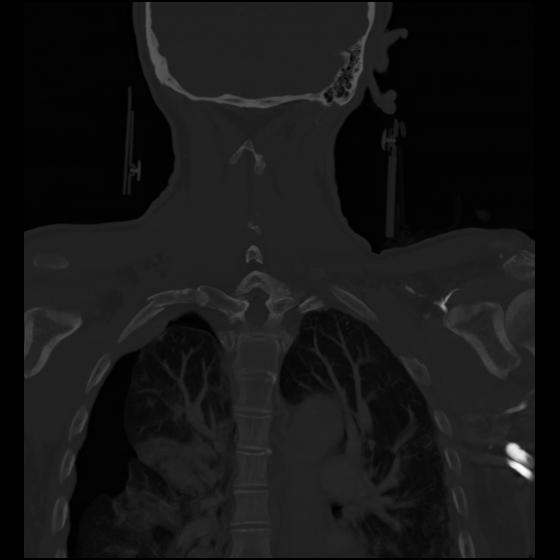

23 ANGIO,CE,Cor-MIP,5.000,ANGIO,Cor-MIP,